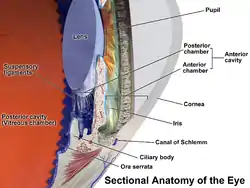

Uveitis (/ˌjuːvi.aɪtɪs/) is inflammation of the uvea, the pigmented layer of the eye between the inner retina and the outer fibrous layer composed of the sclera and cornea.[1] The uvea consists of the middle layer of pigmented vascular structures of the eye and includes the iris, ciliary body, and choroid. Uveitis is described anatomically, by the part of the eye affected, as anterior, intermediate or posterior, or panuveitic if all parts are involved. Anterior uveitis (iridocyclitis) is the most common, with the incidence of uveitis overall affecting approximately 1:4500, most commonly those between the ages of 20-60. Symptoms include eye pain, eye redness, floaters and blurred vision, and ophthalmic examination may show dilated ciliary blood vessels and the presence of cells in the anterior chamber. Uveitis may arise spontaneously, have a genetic component, or be associated with an autoimmune disease or infection. While the eye is a relatively protected environment, its immune mechanisms may be overcome resulting in inflammation and tissue destruction associated with T-cell activation.

Uveitis is classified anatomically into anterior, intermediate, posterior, and panuveitis forms—based on the part of the eye primarily affected.[2] Before the twentieth century, uveitis was typically referred to in English as "ophthalmia."[3]

- Anterior uveitis includes iridocyclitis and iritis. Iritis is the inflammation of the anterior chamber and iris. Iridocyclitis is inflammation of the iris and ciliary body with inflammation predominantly confined to the ciliary body. Between 66% and 90% of uveitis cases are anterior in location (iritis).[4] This condition can occur as a single episode and subside with proper treatment or may take on a recurrent or chronic nature.

- Intermediate uveitis, also known as pars planitis, consists of vitritis—which is inflammation of cells in the vitreous cavity, sometimes with snowbanking, or deposition of inflammatory material on the pars plana. There are also "snowballs," which are inflammatory cells in the vitreous.

- Posterior uveitis or chorioretinitis is the inflammation of the retina and choroid.

- Panuveitis is the inflammation of all layers of the uvea.